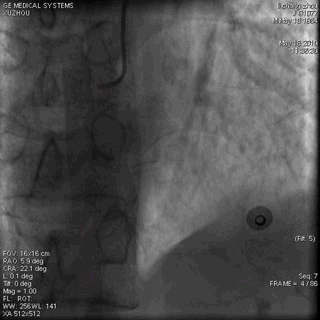

在简短沟通并签好心导管检查治疗同意书后,大家熟练消毒,铺巾,穿刺桡动脉。一切都在紧张有序的进行中,大约10分钟,造影检查结果出来了。

正常,冠脉造影正常。

(右冠脉造影)